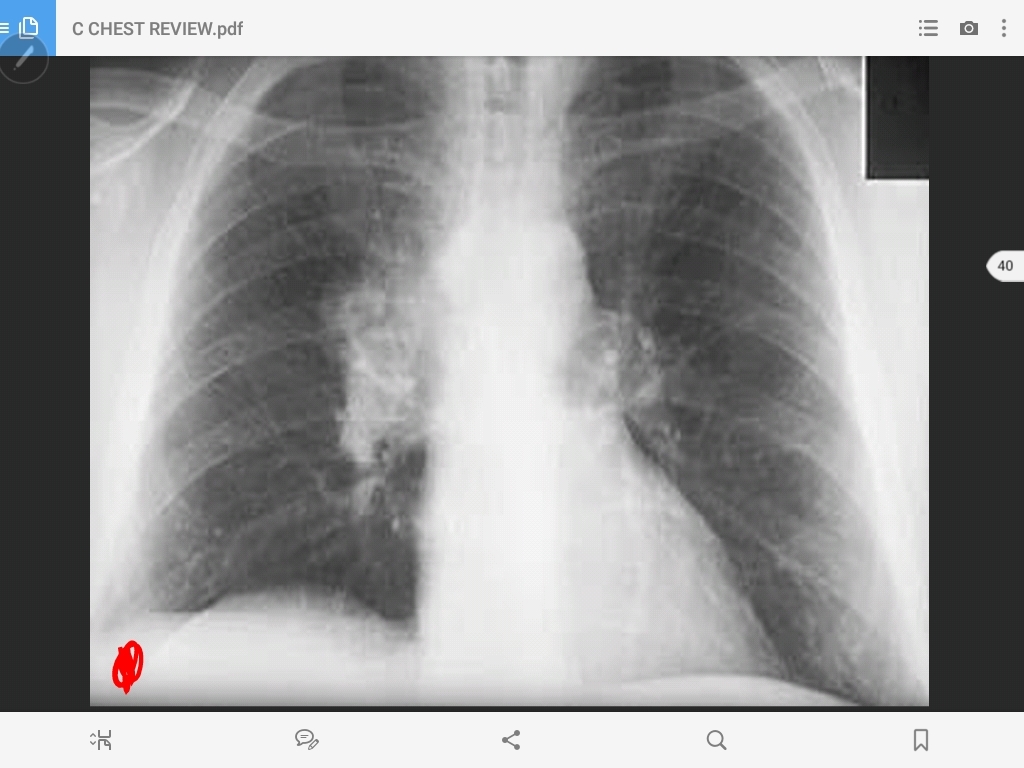

pulmonary metastasis